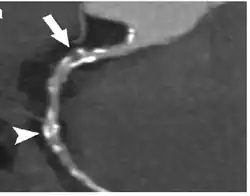

- Tomografia komputerowa (TK) – w odróżnieniu od koronarografii przezskórnej, jest metodą nieinwazyjną, którą ponadto można wykonać w trybie ambulatoryjnym, tym samym redukując szansę wystąpienia powikłań. Umożliwia wykonanie rekonstrukcji w dowolnych płaszczyznach oraz rekonstrukcji przestrzennych. Zapewnia lepszą ocenę zwapnień w obrębie blaszki miażdżycowej oraz ocenę przebiegu i obwodów niedrożnych tętnic wieńcowych. Wadą tej metody jest niższa rozdzielczość przestrzenna i czasowa w porównaniu z tą uzyskiwaną w tradycyjnej angiografii. Metoda ta cechuje się najwyższą wartością diagnostyczną spośród metod nieinwazyjnych stosowanych w diagnostyce choroby wieńcowej serca. Tomografia komputerowa stosowana jest do oceny anomalii tętnic wieńcowych, mostków mięśniowych przebiegających nad tętnicami wieńcowymi, przetok, badania pomostów aortalno-wieńcowych[7].